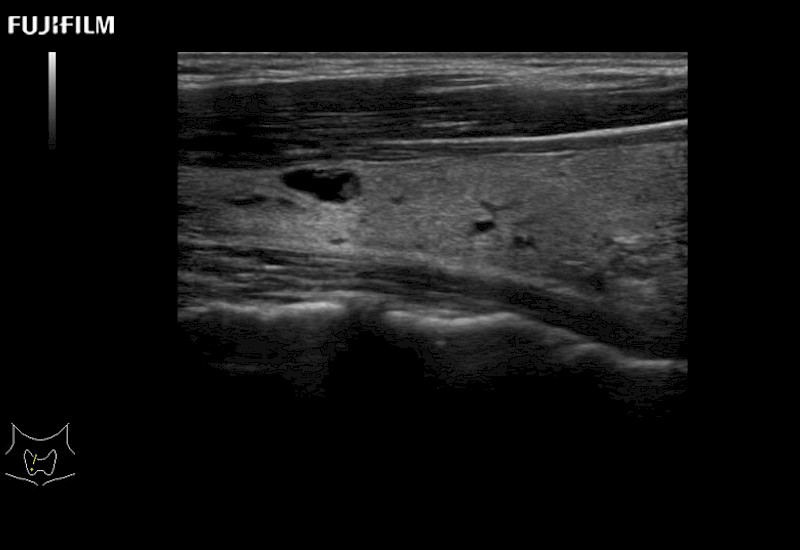

Linear array side-fire “T” transducer for open surgical procedures.

Main Specifications: